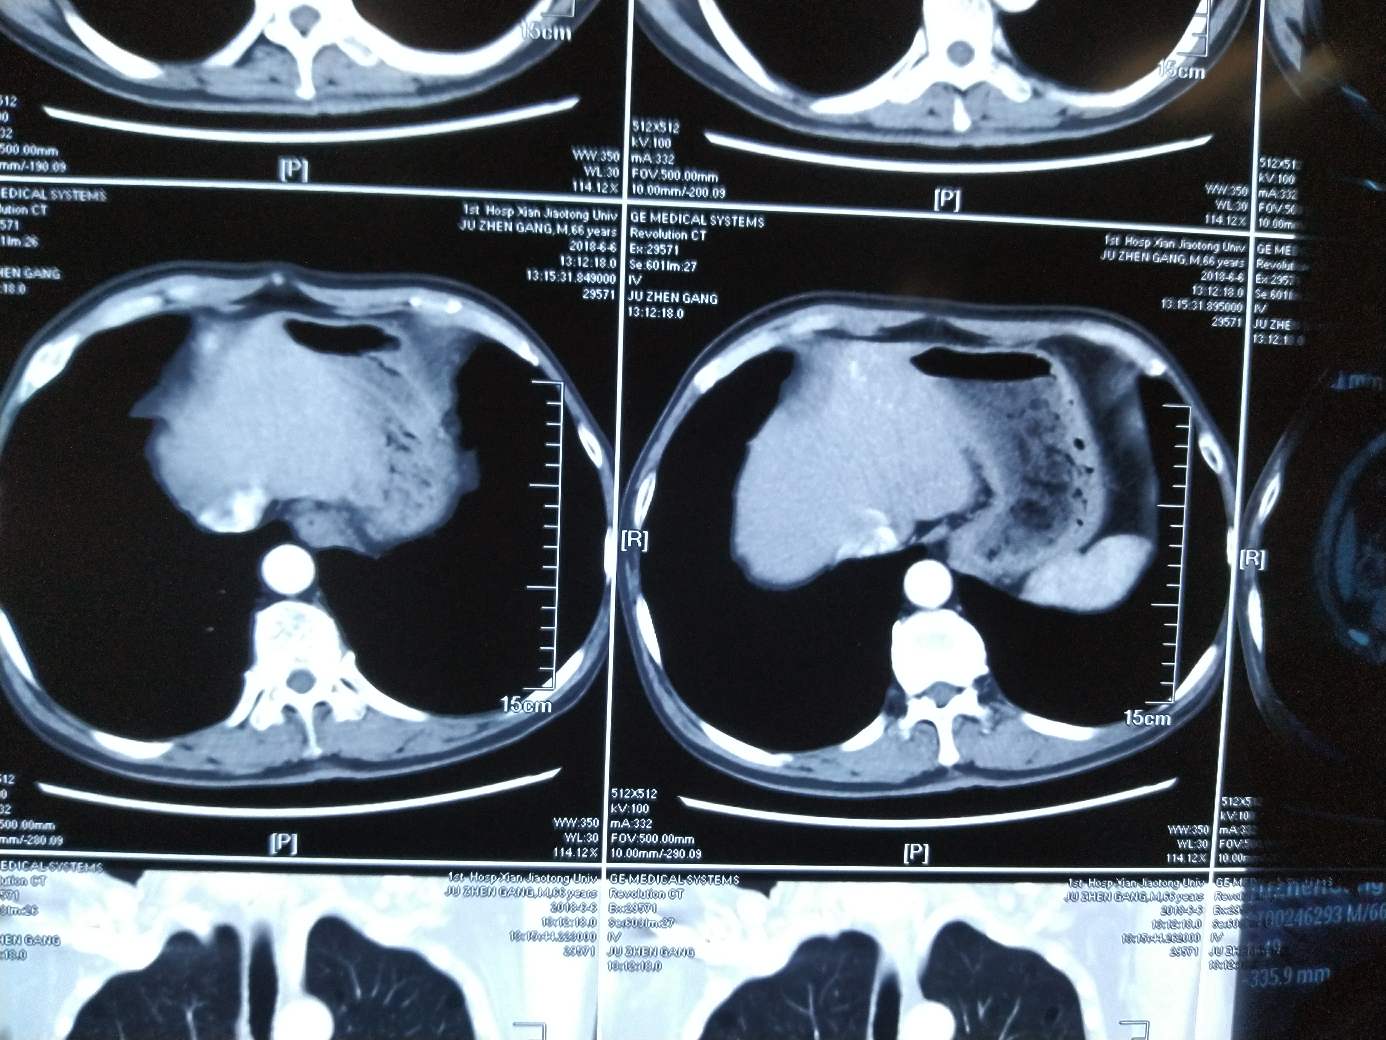

左下角发白位置是肝转移